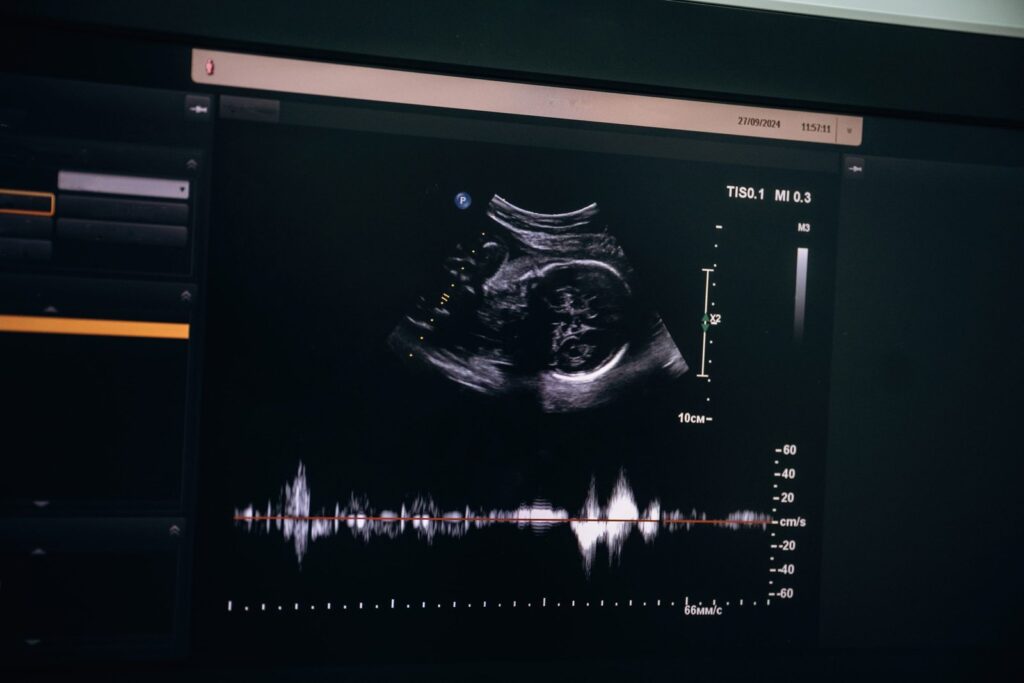

Ao contrário do que muitos imaginam, os ultrassons não servem apenas para “ver o bebê”. Cada exame tem um objetivo específico e um papel importante na avaliação da saúde materna e fetal. Quando realizados nos períodos corretos e com tecnologia adequada, eles ajudam a antecipar riscos, confirmar o desenvolvimento saudável e fortalecer o vínculo entre gestante, bebê e equipe médica.

O Doppler obstétrico representa um diferencial tecnológico importante dentro do cronograma de ultrassons na gestação. Ele avalia o fluxo sanguíneo entre mãe, placenta e bebê, fornecendo dados essenciais sobre oxigenação e nutrição fetal.

Esse exame auxilia no monitoramento e na prevenção de condições como a pré-eclâmpsia, além de identificar possíveis restrições de crescimento intrauterino. Em gestações de risco, o Doppler se torna uma ferramenta indispensável para decisões clínicas mais seguras e assertivas.